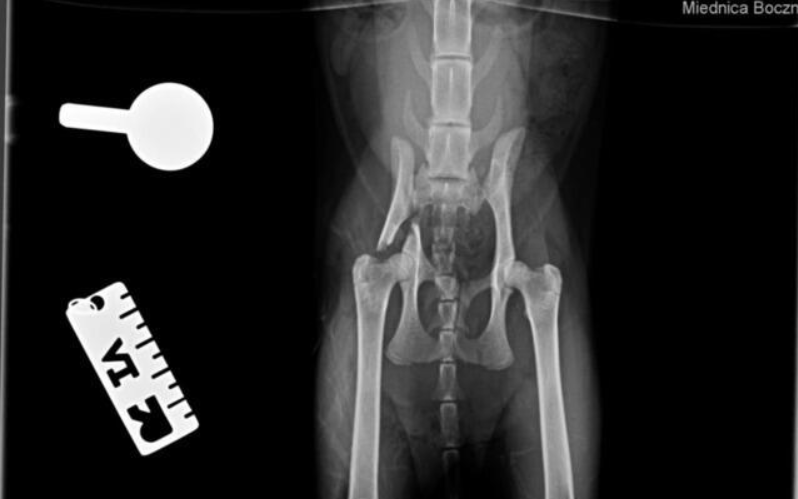

Kotka została znaleziona pod blokiem przez cudowną osobę, która nie pozostała obojętna i natychmiast powiadomiła odpowiednie służby! W wyniku upadku Felcia odniosła bardzo poważne obrażenia: przesunięcie kręgów w odcinku krzyżowym kręgosłupa, złamanie miednicy i zwichnięcie stawu biodrowego. Na szczęście zachowała czucie, więc mamy wielką nadzieję na powrót małej do pełnej sprawności, do czego długa droga...

Kicia jest już pod opieką naszej fundacji! Jest już po skomplikowanej operacji, której podjął się znakomity ortopeda, doktor Kacper Weigel. Z całego serca dziękujemy Panu doktorowi oraz całemu zespołowi Kliniki Weterynaryjnej Puławska za błyskawiczną pomoc i zaangażowanie! Wszystko się udało i po 6 tygodniowym unieruchomieniu w kennelu rozpoczniemy rehabilitację.